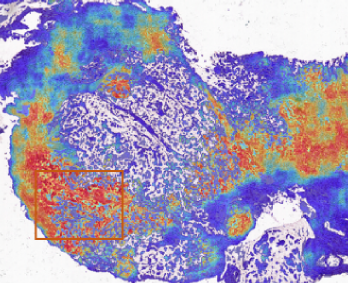

Block interception and precise amplification of gastric biopsy digital images; Tumor segmentation model

and heat map analysis; Feature extraction, negative and positive classification to predict tumor probability with high sensitivity.

2. Thermal analysis: show the risk level in each area, locate abnormal follicular cells and make an intelligent rank for quick review,

visualize each phase and one-click for online report.

3. WSI reasoning: WSI slide-window reasoning, intelligent zoom in, adenoma identification optimization.